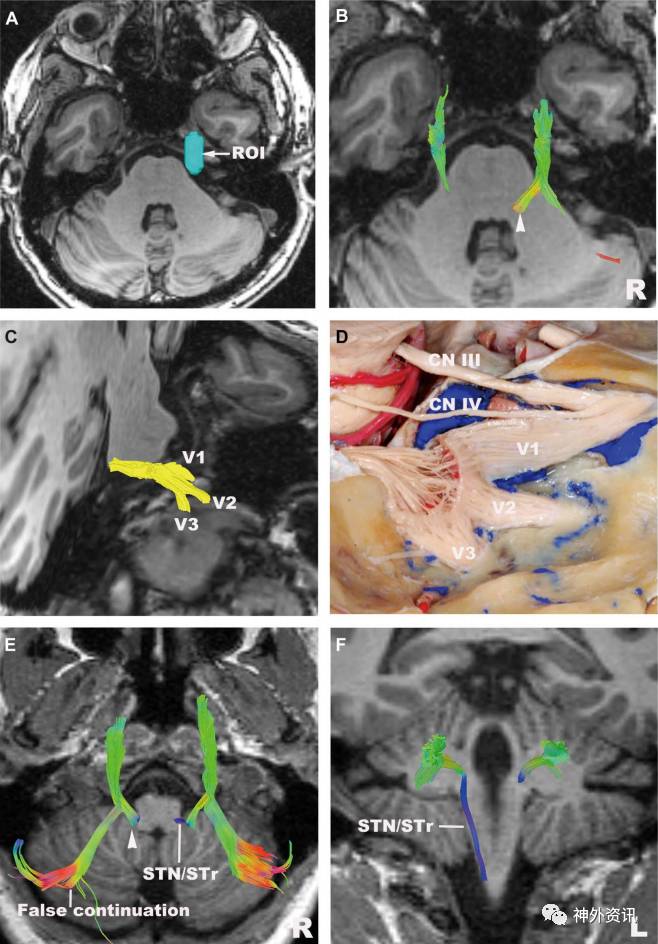

图6. 三叉神经。A.ROI置于脑池段;B.三叉神经,重建三叉神经止于脑桥部;C.三叉神经(斜位),重建眼神经(V1)、上颌神经(V2)和下颌神经(V3);D.对应C图的解剖示图(侧位);E.三叉神经(轴位);F.三叉神经(冠状位);重建左侧三叉神经止于脑桥部(箭头),右侧三叉神经于脑干处下降,重建出入小脑的纤维束,但并没有对应于正常结构。STN:脊髓三叉神经核;STr:脊髓三叉神经束。